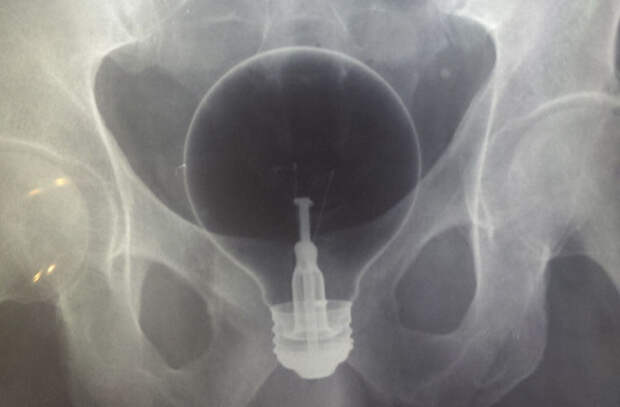

Здесь и далее: инородные предметы внутри человека, рентген

Американцу Фредерику Хелзелу его шокирующие исследования научного признания не принесли. Еще в подростковом возрасте он стал придерживаться странной диеты для снижения веса. Он поглощал перья, опилки, асбест, а хирургическая вата стала частью его ежедневного рациона. Позже, уже работая в Университете Чикаго, в 1920-е годы Хелзел проводил над собой сомнительные опыты, чтобы выявить время выведения из организма различных несъедобных материалов. Экспериментальным путем он выяснил, что стеклянные бусины проходят через желудочно-кишечный тракт за 40 часов, гравий покидает организм спустя 52 часа после проглатывания, а золотые шарики выходят только через 22 дня. Помимо истощенного организма и славы чудаковатого исследователя («человек-козел» — прозвали его репортеры того времени) никаких плодотворных результатов «желудочные» опыты Хелзела не дали, а сам он так и остался работать при университете научным ассистентом.